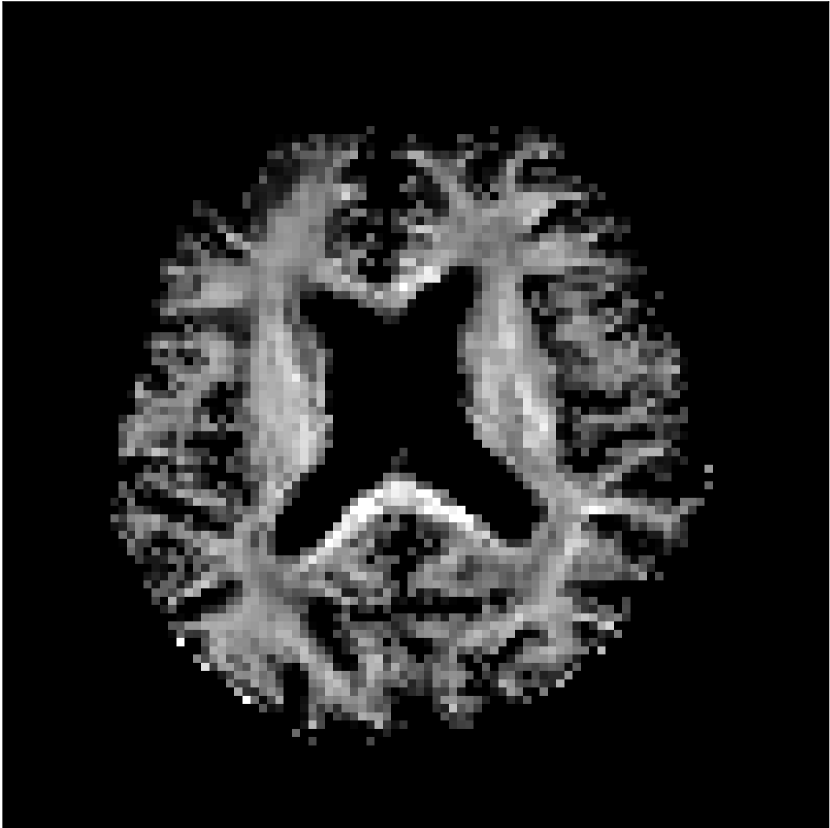

Figure 8 shows examples of non-diffusion-weighted images before and after processing. The raw images (Raw) served as the input for the magnitude deep learning (MCNN) and complex deep learning (CCNN) methods.

Raw 𝐱tsubscript𝐱𝑡\mathbf{x}_{t}

MCNN, fθ^(𝐱t)subscript𝑓^𝜃subscript𝐱𝑡f_{\hat{\theta}}\left(\mathbf{x}_{t}\right)

MCNN Resid., Ric(𝐱t)fθ^(𝐱t)Ricsubscript𝐱𝑡subscript𝑓^𝜃subscript𝐱𝑡\text{Ric}(\mathbf{x}_{t})-f_{\hat{\theta}}\left(\mathbf{x}_{t}\right)

CCNN, fθ^(𝐱t)subscript𝑓^𝜃subscript𝐱𝑡f_{\hat{\theta}}\left(\mathbf{x}_{t}\right)

CCNN Resid., Ric(𝐱t)fθ^(𝐱t)Ricsubscript𝐱𝑡subscript𝑓^𝜃subscript𝐱𝑡\text{Ric}(\mathbf{x}_{t})-f_{\hat{\theta}}\left(\mathbf{x}_{t}\right)

No PF

5/8 PF

Figure 8: Examples of non-diffusion-weighted images from in vivo data at b=0𝑏0b=0 s/mm2. Artifacts in the Raw image, 𝐱tsubscript𝐱𝑡\mathbf{x}_{t}, are corrected by the MCNN and CCNN models, fθ^(𝐱t)subscript𝑓^𝜃subscript𝐱𝑡f_{\hat{\theta}}(\mathbf{x}_{t}). Also shown are the residuals between the CNN corrections and the original Raw image with Rician bias correction Ric(𝐱t)Ricsubscript𝐱𝑡\text{Ric}(\mathbf{x}_{t}) [10]. The Gibbs artifacts removed by the methods are observed in the residuals. The MCNN method introduces some banding artifacts at the PF 5/8ths factor that are not present in the CCNN method.

Both methods remove artifacts, but the MCNN method allows residual rippling artifacts to pass through in the presence of partial Fourier. These rippling artifacts are not present in the CCNN method.